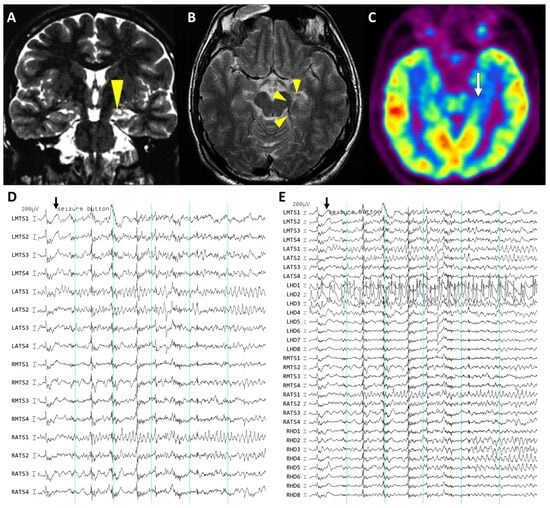

2.2.1. Presurgical Evaluations

2.2.2. Surgical Procedures for Invasive Studies

2.2.3. Clinical Assessment of Intracranial EEG Recording

2.3. Characterization of the Ictal Onset Patterns of Depth and Subdural Electrodes

3.2. Electrographic Patterns at Ictal Onset

3.3. Distribution of Involved Electrodes and False Lateralization